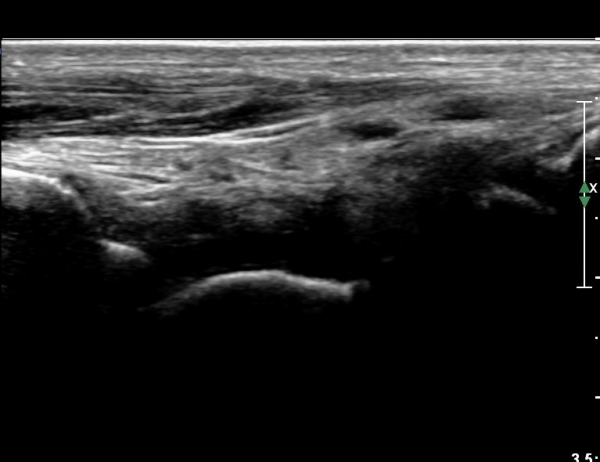

¹ß¸ñ À§¿¡¼­ ¸»´Ü ¾ÕÂÊ °æ°ñºñ°ñÀδë Á¾´Ü¸é°Ë»ç¿¡¼­ ƯÀÌ ¼Ò°ßÀ» º¸ÀÌÁö ¾Ê´Â´Ù(»çÁø 2, 3).